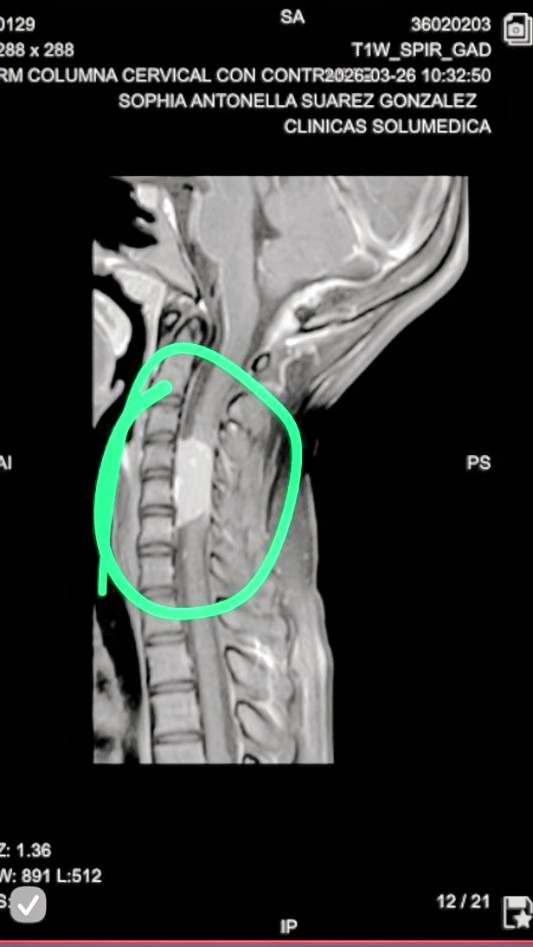

Our beloved Sophia, just 12 years old, is the daughter of my cousin and a bright, loving child who means everything to our family. Recently, our lives were turned upside down when she was diagnosed with a space-occupying lesion (SOL) in her spinal cord—a serious and delicate condition that requires urgent surgery.

Nuestra querida Sophia, de tan solo 12 años, es hija de mi prima y una niña alegre y amorosa que significa todo para nuestra familia. Recientemente, nuestras vidas dieron un giro inesperado cuando fue diagnosticada con una lesión ocupante de espacio (LOE) en su médula espinal—una condición delicada y grave que requiere una cirugía urgente.